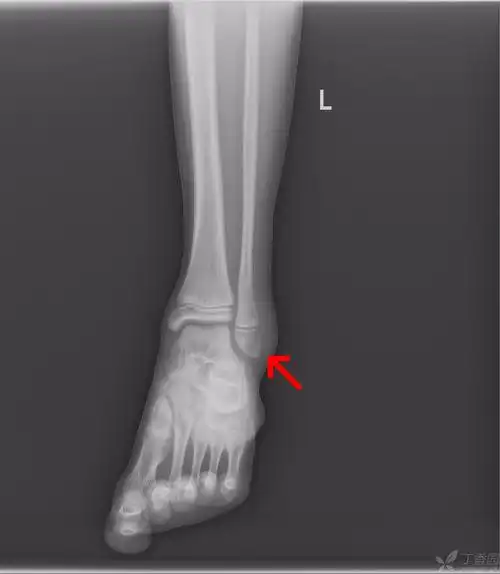

39-外踝骨折 m11y外伤后左外踝肿痛,活动受限1小时余